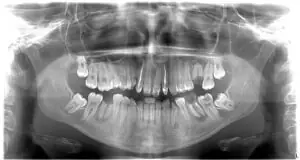

Pacijentkinja, uzrasta 17 godina, javila se u ordinaciju nakon ortodontske terapije koju je sprovodila kako bi ispravila položaj zuba i poboljšala funkcionalnost vilice.

Nakon skidanja aparata, primećeno je da su neki zubi oštećeni, dok su neki morali biti izvađeni zbog trauma i prethodnih oštećenja.

Rendgen snimak pre počekta rada